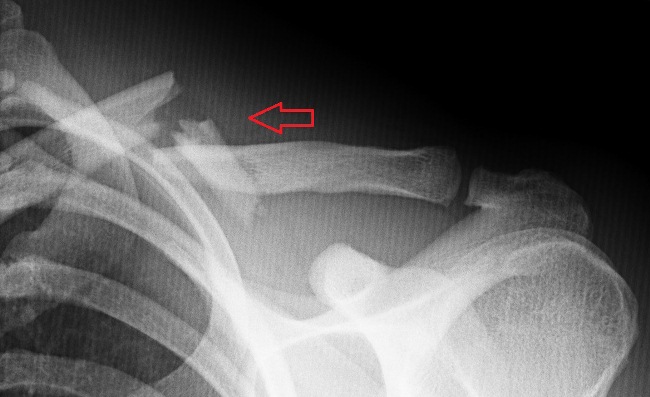

Полный перелом ключицы

Перелом ключицы можно определить визуально